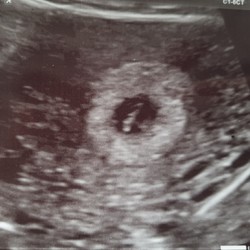

Het hartje is met 8 weken zeker te zien! Wij hebben gister het hartje al ge ...

Klopt dat er met een inwendig echo een hartje is te zien. Ik ben alleen benieuwd of dit uitwendig ook zo is.

Ja! Maandag een echo (uitwendig) gehad met 8+2. Mooi hartje gezien 😊

Met 6 weken en 3 dagen ook al een kloppen hartje te zien, uitwendig.